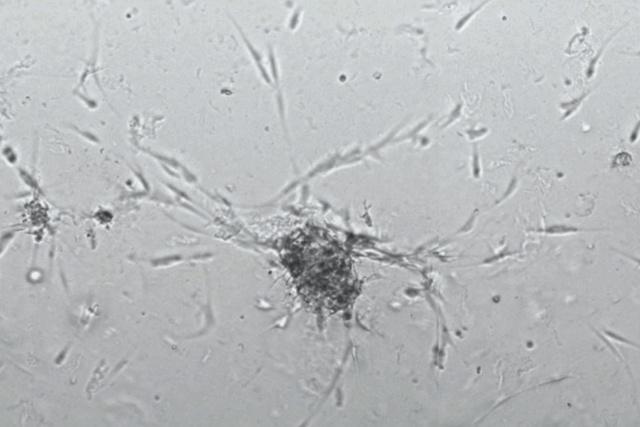

Cutaneous neurofibroma organoids growing in the lab

Cutaneous neurofibroma organoids. Photo courtesy of the Soragni laboratory.

The lack of therapies is partly due to the fact that cutaneous neurofibromas are composed of many different cell types and abundant extracellular proteins, making it difficult to model them in the lab to study. To meet these challenges, Soragni and her team has developed a high throughput organoid screening platform to rapidly establish and screen 3D tumor organoids for cutaneous neurofibromas to find drugs that slow tumor growth, supported by a 2018 grant from the Neurofibromatosis Therapeutic Acceleration Program.

The screening method, described in the journal Cell Reports Methods, uses patients’ own tumor cells, collected during surgery, to create miniature patient-derived tumor organoids. The organoids mimic the characteristics of the tumor they originated from.

By optimizing growth conditions, the team was able to establish patient-derived cutaneous neurofibroma organoids from several patients with NF1, and to show how cutaneous neurofibroma organoids recapitulate the critical features of parental tumors. They also implemented their mini-ring high throughput screening platform to find drugs slowing organoid growth.